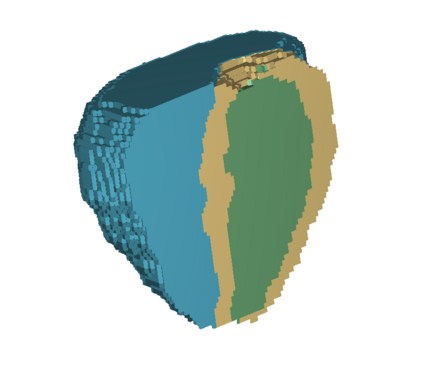

In cardiac magnetic resonance (CMR) imaging, a 3D high-resolution segmentation of the heart is essential for detailed description of its anatomical structures. However, due to the limit of acquisition duration and respiratory/cardiac motion, stacks of multi-slice 2D images are acquired in clinical routine. The segmentation of these images provides a low-resolution representation of cardiac anatomy, which may contain artefacts caused by motion. Here we propose a novel latent optimisation framework that jointly performs motion correction and super resolution for cardiac image segmentations. Given a low-resolution segmentation as input, the framework accounts for inter-slice motion in cardiac MR imaging and super-resolves the input into a high-resolution segmentation consistent with input. A multi-view loss is incorporated to leverage information from both short-axis view and long-axis view of cardiac imaging. To solve the inverse problem, iterative optimisation is performed in a latent space, which ensures the anatomical plausibility. This alleviates the need of paired low-resolution and high-resolution images for supervised learning. Experiments on two cardiac MR datasets show that the proposed framework achieves high performance, comparable to state-of-the-art super-resolution approaches and with better cross-domain generalisability and anatomical plausibility.